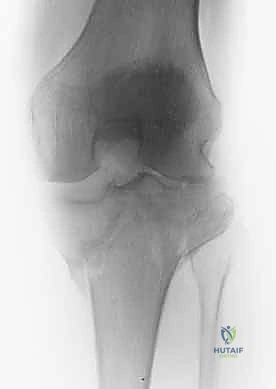

2. التصوير الإشعاعي (X-rays)

الخطوة الأولى هي التقاط صور أشعة سينية من عدة زوايا (أمامية خلفية، وجانبية). تعطي الأشعة السينية فكرة عامة عن وجود الكسر وموقعه، لكنها غير كافية لتقييم الكسور ثنائية اللقمة المعقدة.

3. الأشعة المقطعية المحوسبة (CT Scan) - المعيار الذهبي

لا يمكن إجراء جراحة لكسر ثنائي اللقمة دون إجراء أشعة مقطعية (يفضل مع إعادة بناء ثلاثية الأبعاد 3D).

* توفر الأشعة المقطعية خريطة دقيقة لكل شظية عظمية.

* تحدد مقدار الانخساف في السطح المفصلي بالمليمتر.

* تكشف الشظايا المخفية، خاصة في الجزء الخلفي من الركبة (Posterior Coronally oriented fragments) والتي تتطلب خطة جراحية خاصة لتثبيتها.